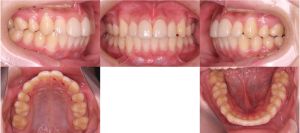

※治療終了時

歯並びが整い、あわせて形にバランスの乱れがあった上の前歯2本は、ラミネートベニアによって自然な見た目に整えられました。

※治療終了時の口腔内写真(正面)

歯科技工士が作製した補綴物は、周囲の歯になじむ自然な見た目に仕上がっています。

※術前(左)と術後(右)

治療後の結果について、患者さまから前向きなお声をいただいています。

※口元の拡大

口元の印象も、自然でバランスの取れた状態となりました。